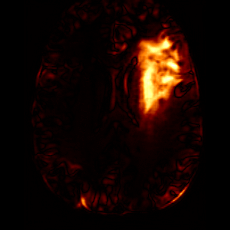

Figure 7: Ablation study of Lesion Consistency Guidance (LCG). Without LCG, the generated pathological regions are indistinct and show weak pathological expression in both examples.

Lesion Consistency Guidance. Fig. 7 illustrates the impact of Lesion Consistency Guidance (LCG) for healthy-to-pathology editing. Without LCG, the generated lesion regions appear blurry around lesion boundaries, and the pathological patterns are less distinct, resulting in ambiguous lesion localization and weak pathological expression. Incorporating LCG produces lesions with more precise localization and well-defined shapes that better align with the given lesion masks, as well as textures and contrasts that exhibit stronger pathological characteristics. These results demonstrate that LCG effectively enforces lesion-aware conditioning, enhancing both spatial and semantic consistency of the generated pathological regions.